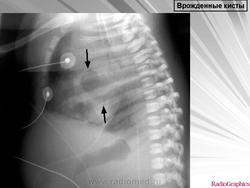

Легочные кисты.

Приложения:

1.ki_.slayd107.jpg2.ki_.slayd108.jpg3.ki_.slayd109.jpg